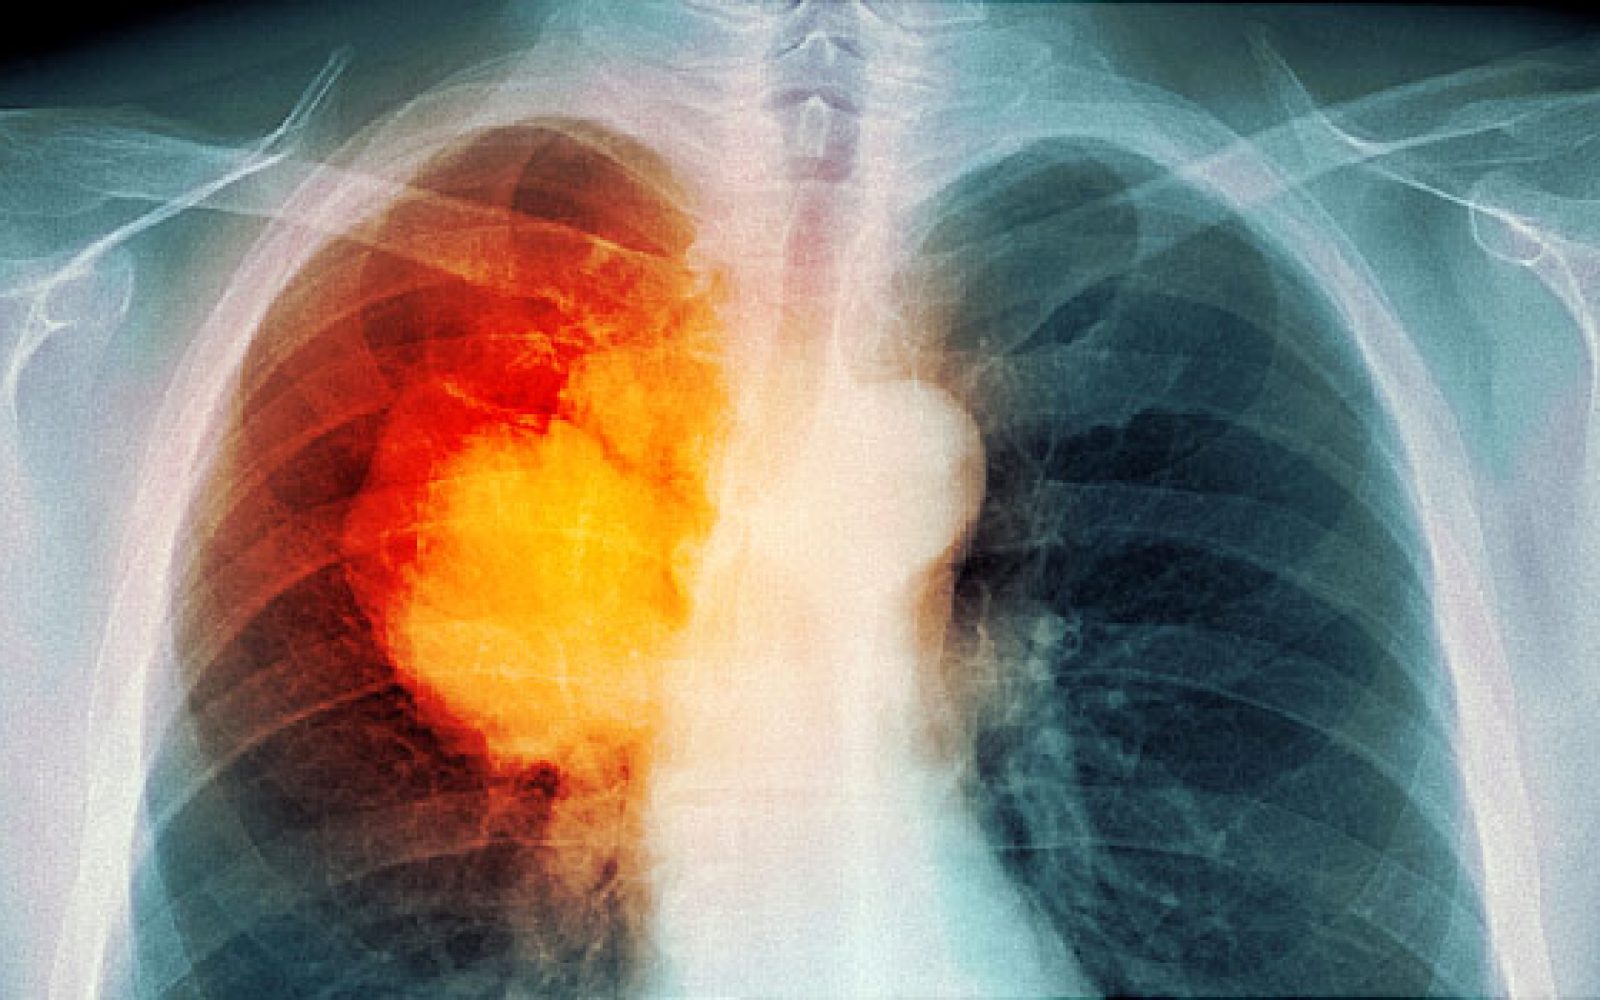

Pljučni rak je vse prej kot redka bolezen, v Sloveniji se namreč vsako leto odkrije tisoč novih bolnikov.

Pljučni rak pri moških upada, pri ženskah pa narašča